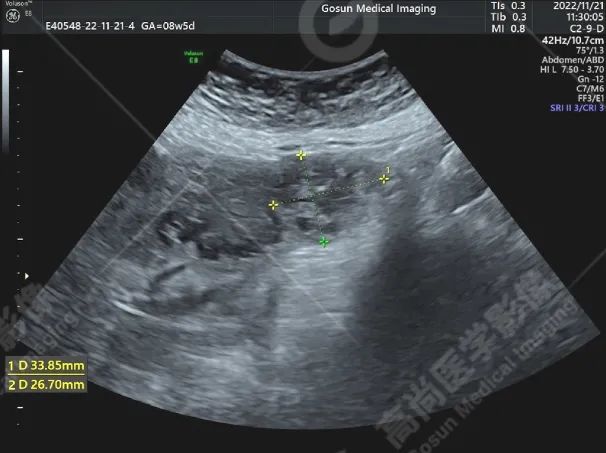

前位子宫,包膜光滑完整,形态饱满,实质回声不均匀增粗,内膜前移、清晰,厚约 15 mm;左侧宫角可见一向外突起的混合回声团块,大小约 34 mm×27 mm,边界欠清,形态尚规则,内部可见多处大小不等的无回声区,内侧与宫腔不相通,外侧肌层不完整,局部仅可见浆膜层,CDFI 显示其内可见丰富血流信号,PW 显示内部 Vp = 45 cm/s,RI = 0.23。

左侧宫角旁混合性包块 (考虑左输卵管间质部妊娠);子宫腺肌病;双侧卵巢未见明显异常。